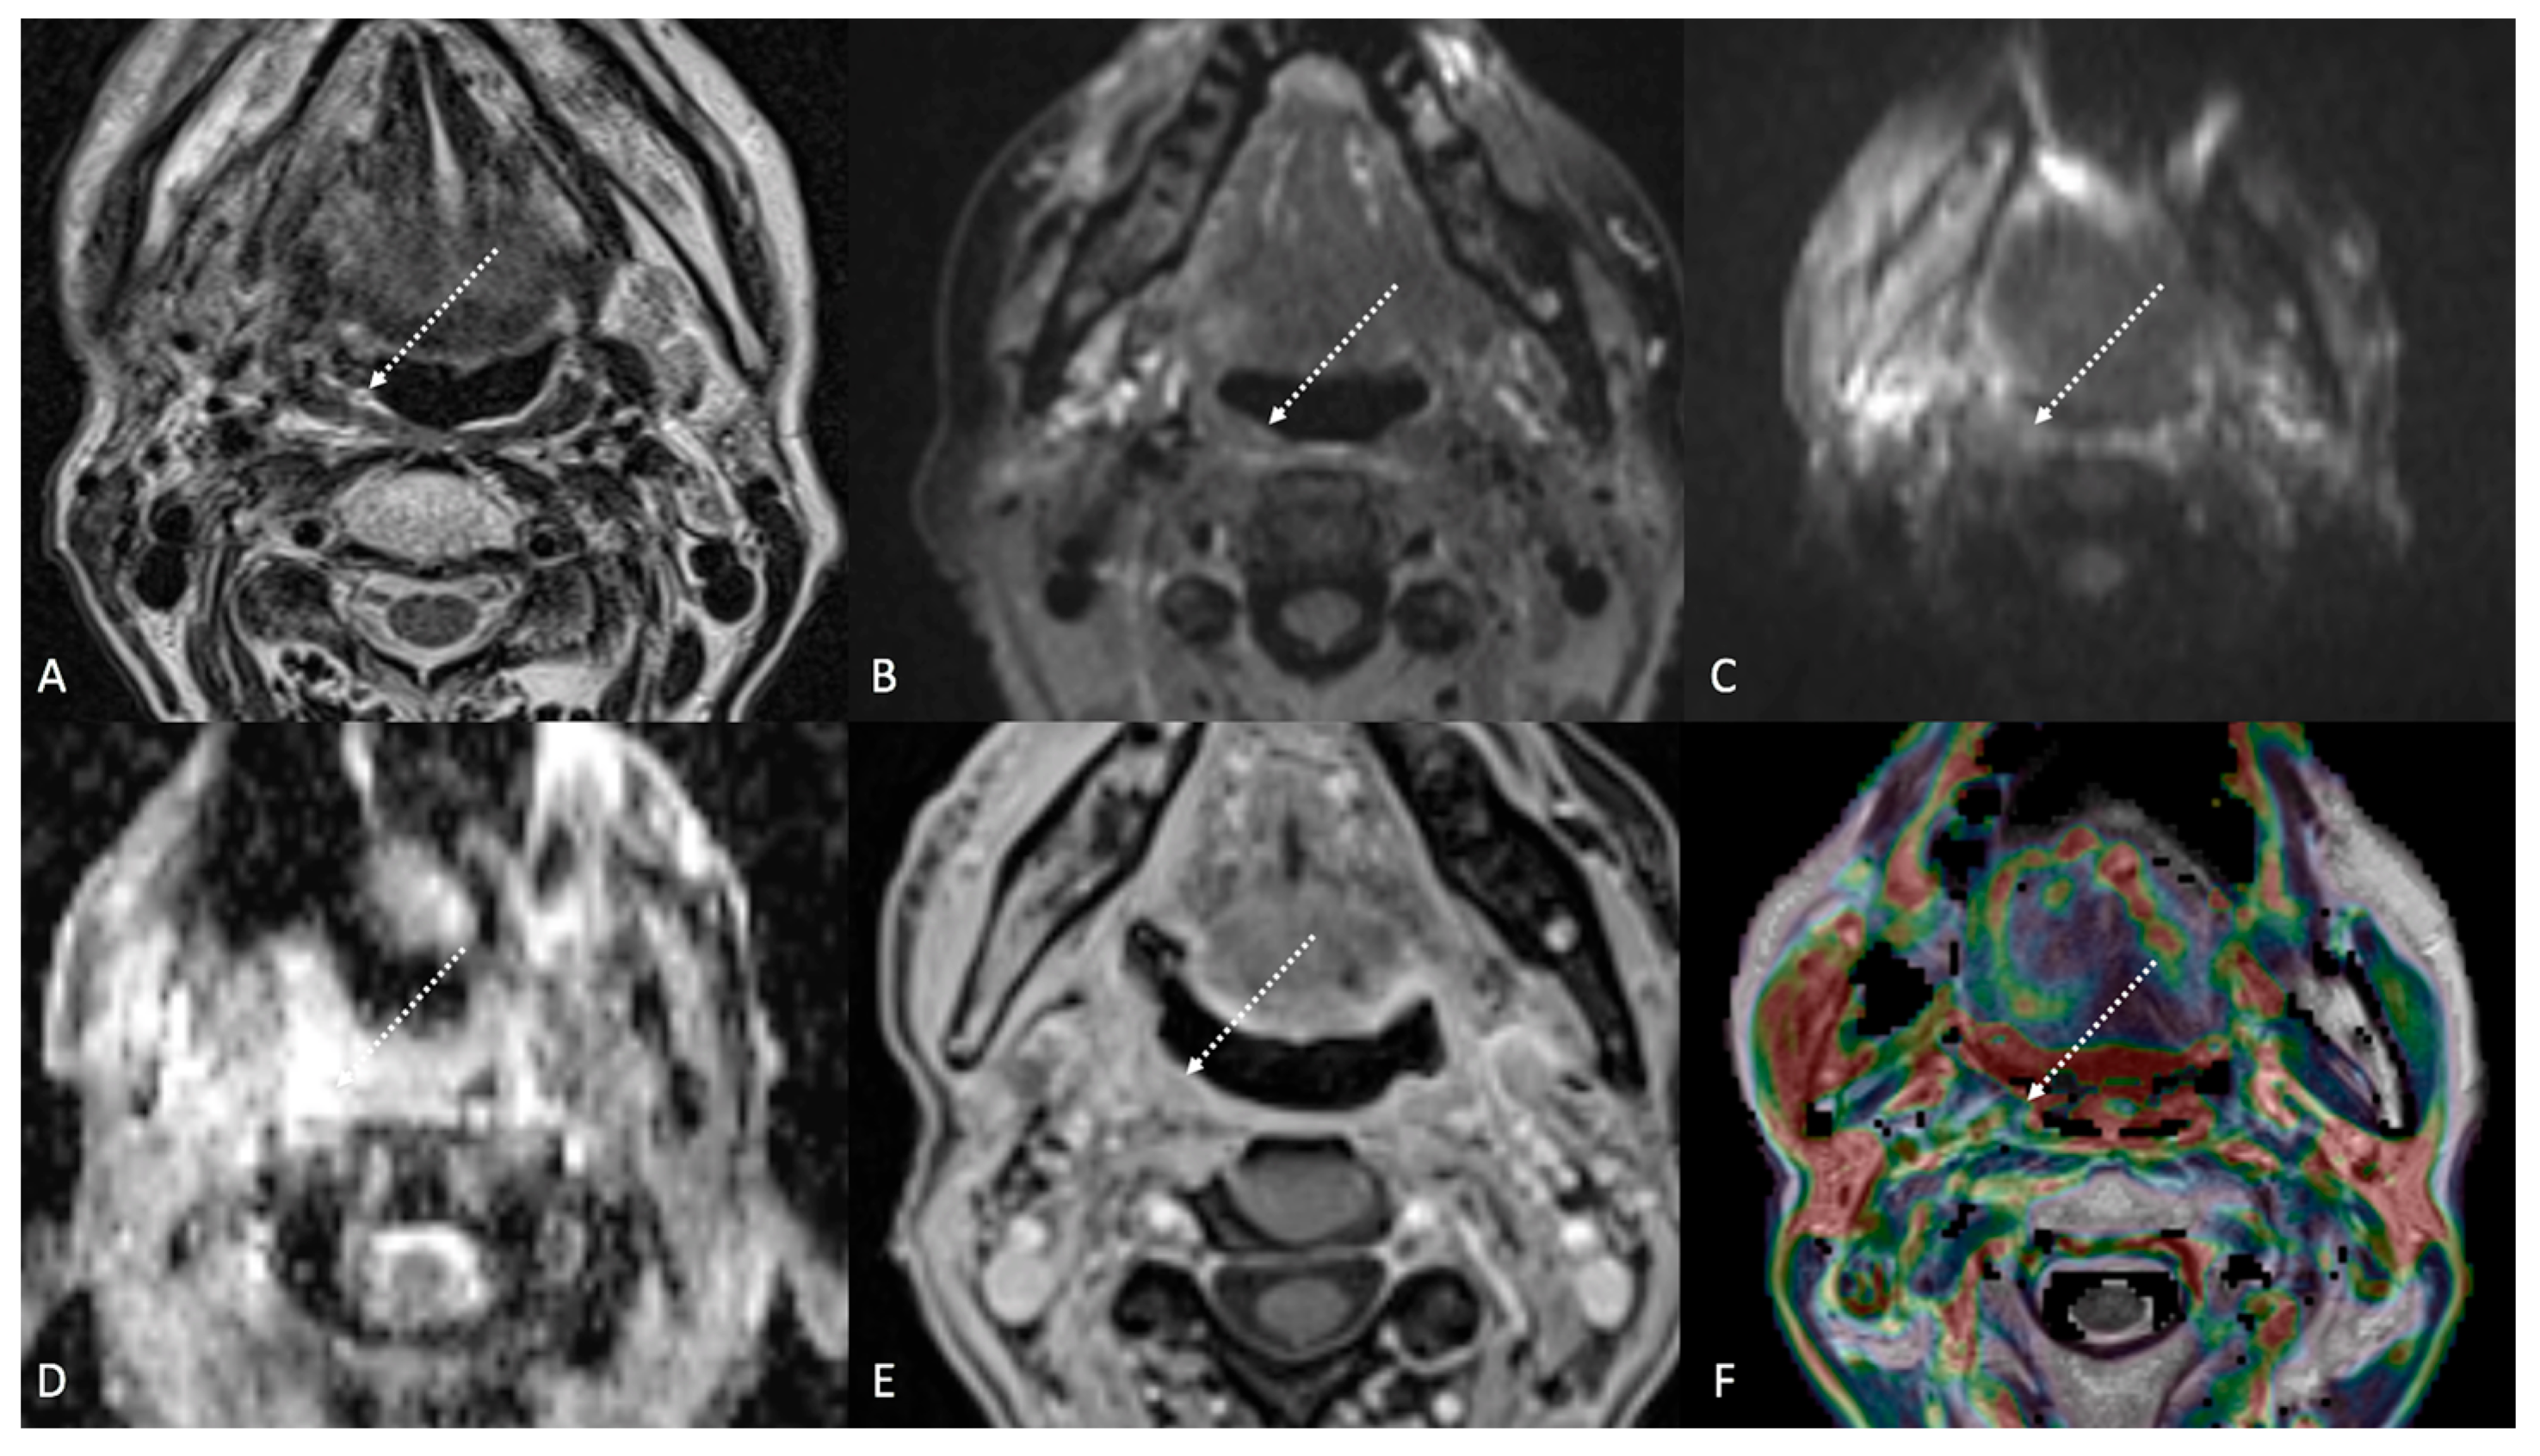

Figure 3.

Post-treatment magnetic resonance imaging (MRI) of a 63-year-old female patient with human-papillomavirus-positive carcinoma of the right palatine tonsil with ipsilateral lymph node metastasis (T2N1) recently treated (3 months before) with chemoradiotherapy (CRT). Post-CRT MRI showed linear fibrotic tissues in the right palatine tonsil (white striped arrows) with hypointense signal intensity on T2-weighted (A), T2-weighted fat-saturated, (B) and diffusion-weighted b800 images (C), and intermediate apparent diffusion coefficient values (1.44 × 10−3 mm2/s) (D). After gadolinium contrast agent injection, post-CRT fibrotic tissue showed no submucosal enhancement (E) and low K(trans) value (48.36 × 10−3 mm2/s) on dynamic contrast enhancement-perfusion weighted imaging (F). Ratio between K(trans) values of the primitive tumor and residual tissue after CRT, standardized with respect to K(trans) value of the ipsilateral trapezius (K(trans)post/pre/muscle), was 0.307. These findings are typical of post-CRT scar tissue.